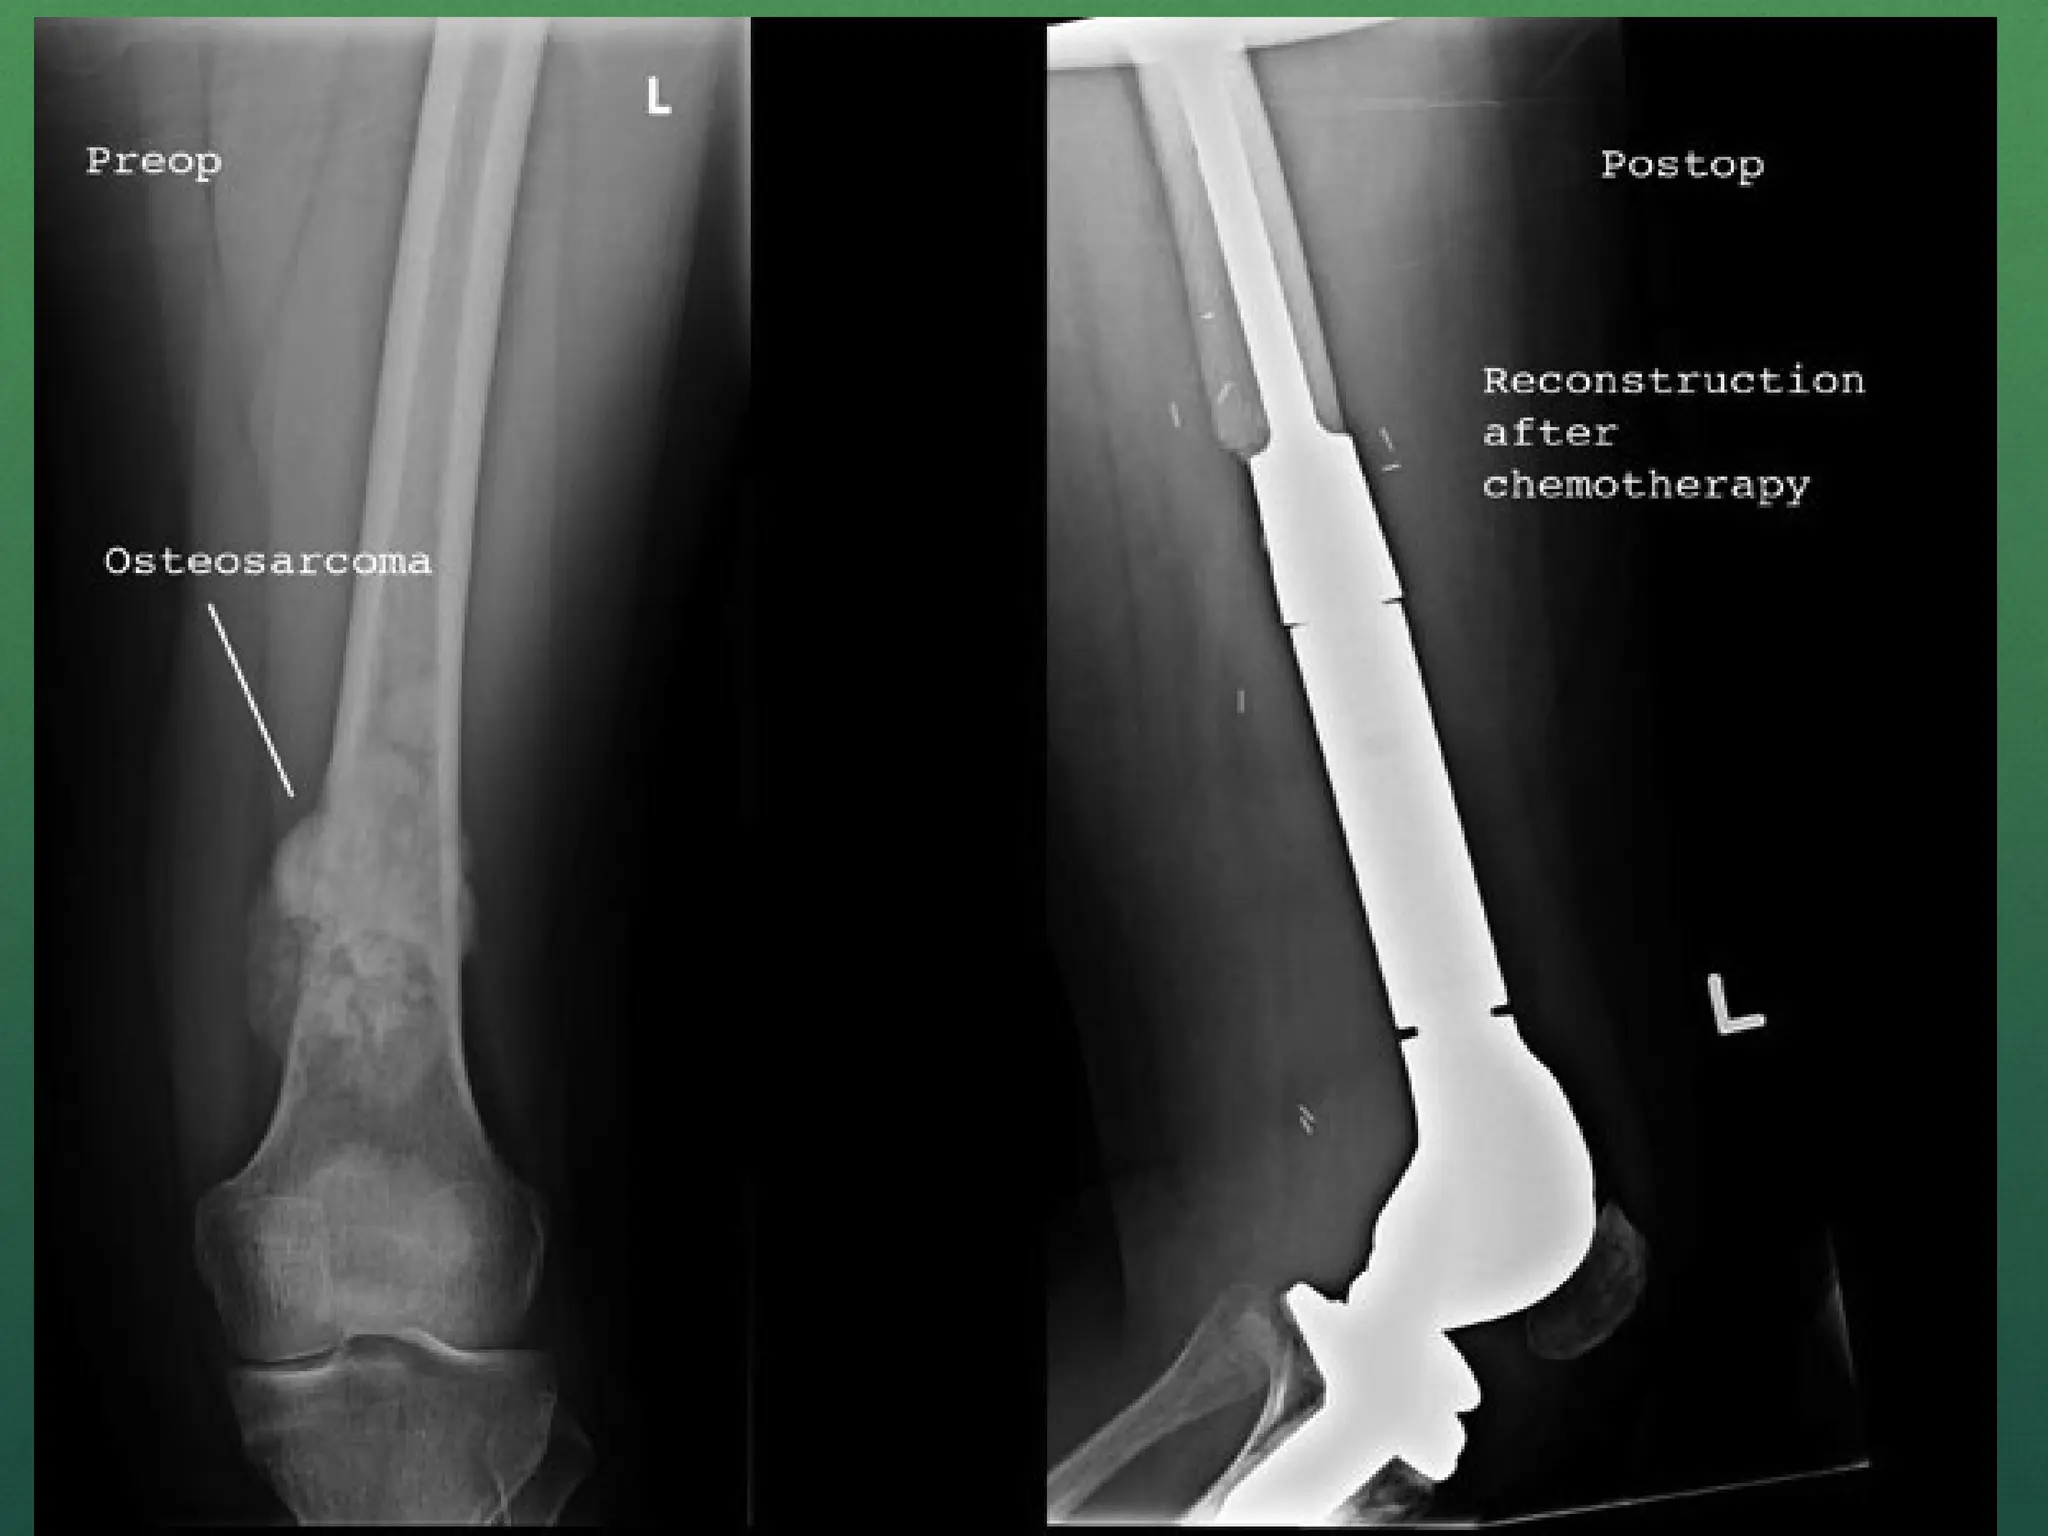

Surgery

 Disarticulation

 Amputation

 Resection with reconstruction/endoprosthesis

 Limb salvage surgery

 Resection of metastatic lesion (lobectomy in lung)

Limb salvage surgery

 Principle is to eradicate the bone tumor, retain integrity of

skeletal system and preserve the limb with useful function.

 After resection, skeletal reconstruction done by bone

grafting(auto or allograft) or by endoprosthesis (modular or

custom made).

 Prosthetic reconstruction is more effective

 As compared to the radical amputation and external

prosthetic fitting or limb sparing surgery with bone grafting

this treatment is more effective in early mobilization.